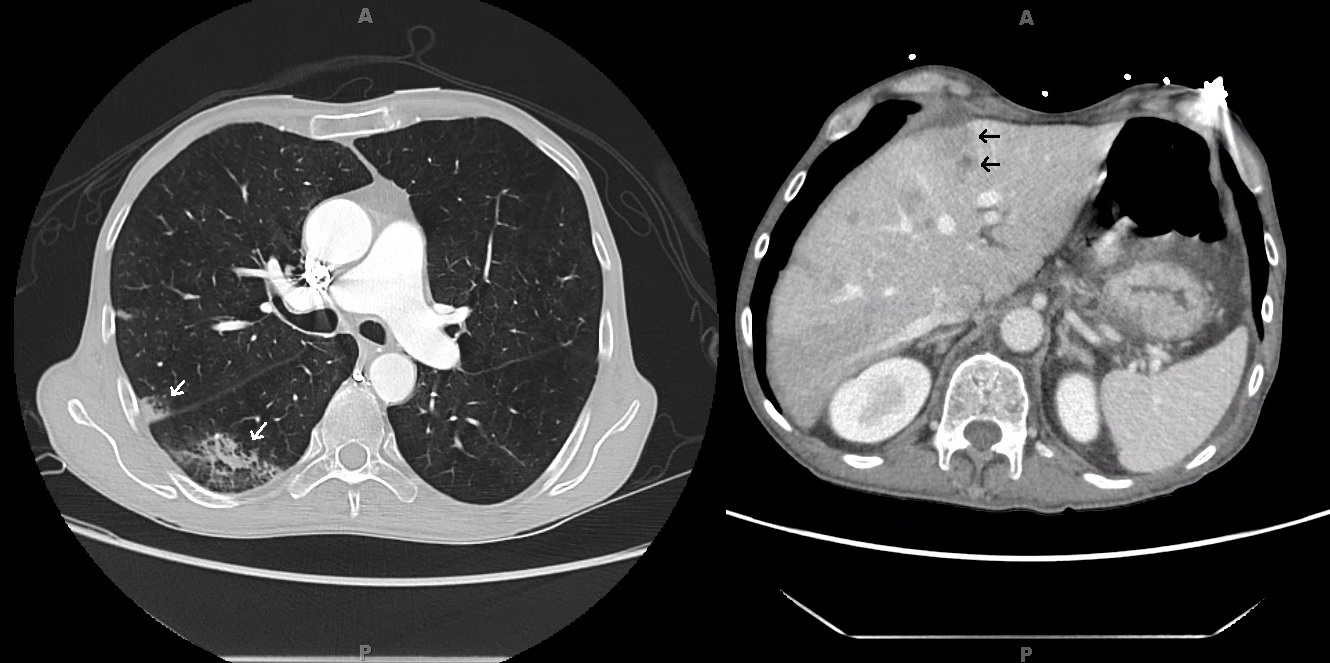

Case Presentation: A 52 year-old man was hospitalized for hypoxia one month after surgery for ruptured appendicitis. He also reported abdominal pain and steatorrhea along with a 50 pound weight loss in five months. On exam he was anicteric but cachectic. CT pulmonary angiogram on admission revealed peripheral-based pulmonary lesions concerning for septic emboli and incidental hepatic lesions. A follow-up CT of the liver revealed multiple small liver lesions and a possible hypo-attenuating pancreatic lesion. His Cancer Antigen 19-9 was 777 U/ml and fecal elastase was undetectable. Our main concern was for pancreatic adenocarcinoma but we considered septic emboli in our differential given his recent ruptured appendicitis. A CT-guided liver biopsy was non-diagnostic with negative cultures of the tissue as well as the blood. Endoscopic ultrasound failed to confirm the patient’s liver lesions. Patient was discharged and readmitted with worsening symptoms and CT findings. Transesophageal echocardiogram revealed thickening and probable small vegetations of the mitral and aortic valves suggestive of non-bacterial thrombotic endocarditis (NBTE). MRI of the abdomen showed a 9×6 mm lesion in the pancreatic head. A repeat liver biopsy resulted with moderately differentiated mucin-producing pancreatic adenocarcinoma. Patient’s repeat CA-19-9 had increased to 6008 U/ml one month after his initial presentation. The patient was diagnosed with metastatic pancreatic adenocarcinoma with systemic emboli from NBTE. He elected to pursue hospice services at home and subsequently discharged from the hospital.

Discussion: When hematogenous spread of infection is on the differential with malignancy, one must be cognizant of NBTE as a cause of systemic embolization. Up to 80% NBTE causes are due to advanced malignancy with lupus coming in a distant second. It is estimated that 10% of patients with mucin-producing adenocarcinoma have NBTE. This patient’s presentation favored pancreatic adenocarcinoma considering his profound weight loss, steatorrhea and elevated CA-19-9. The variation in the appearance of his hepatic and pancreatic lesions on different imaging modalities and the negative initial liver biopsy delayed the diagnosis as extensive infectious workup for septic emboli was pursued. The prognosis of NBTE is poor due to its association with advanced malignancy. As illustrated by this patient’s case, mortality in pancreatic adenocarcinoma approaches 80% in the first year of diagnosis due to its late presentation.